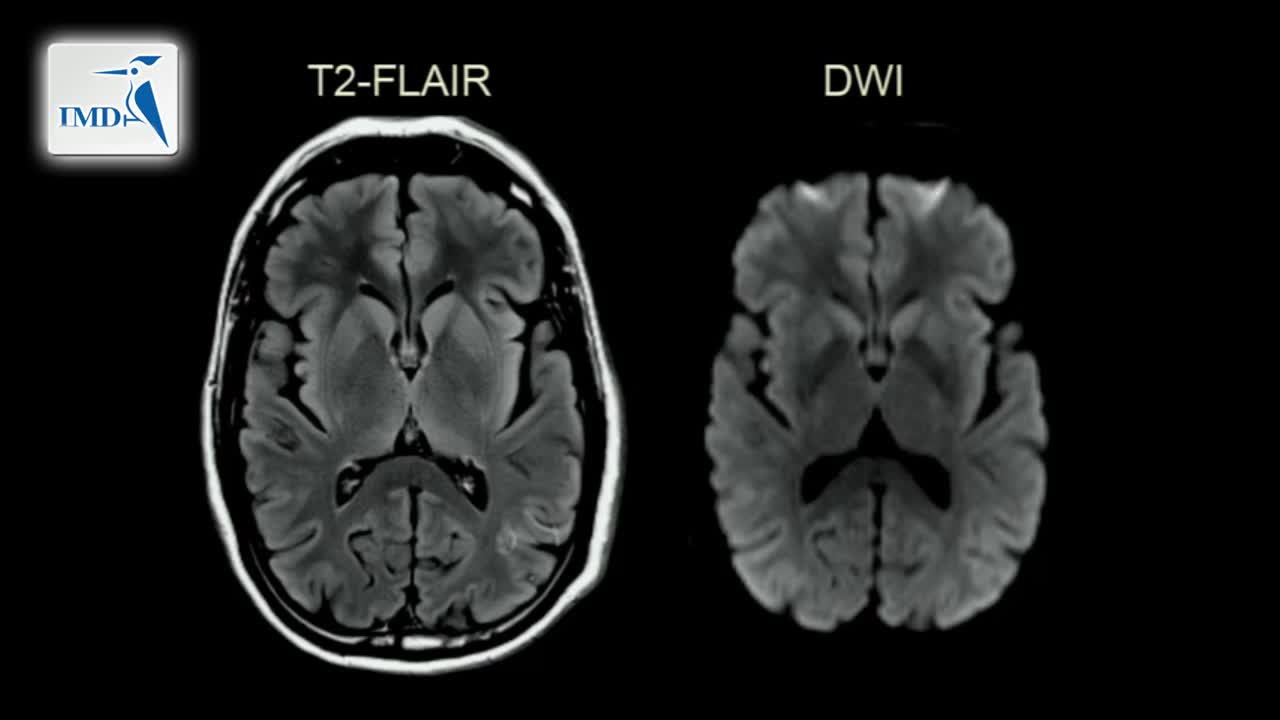

《神经科》2019年第4讲(总第159讲)基于病例学习神经影像学(4)

《神经科》2019年第2讲(总第157讲)基于病例学习神经影像学(2)

《神经科》2019年第1讲(总第156讲)基于病例学习神经影像学(1)